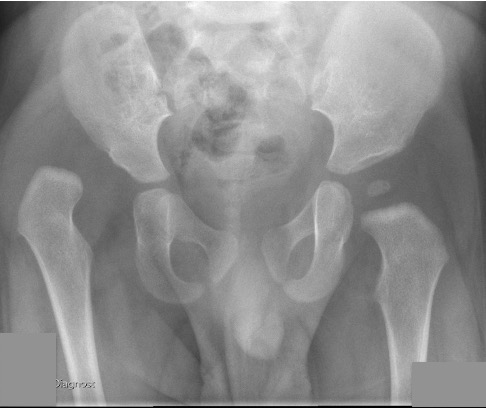

Xray

Dislocated hips in the setting of DDH with ncreased acetabular index